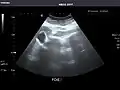

Abdominal Ultrasound (Full Exam)

STRUCTURED REPORT

(Technique: Transabdominal ultrasonography; Device: Toshiba Aplio XG)

Liver: Diffusely homogeneous and normal in echogenicity. No focal mass or contour nodularity. No intrahepatic biliary ductal dilatation.

Portal Vein: Patent main portal vein.

Gallbladder: No stones, wall thickening, or pericholecystic fluid.

Common Bile Duct: Nondilated measuring 1.3 mm at the level of the porta hepatis.

Pancreas: Visualized portions unremarkable.

Spleen: Normal in size.

Kidneys: Right and left kidneys measure 11.5 cm and 12 cm in length respectively. No hydronephrosis. Small left lower pole kidney cyst.

Ascites: None.

Aorta: Visualized portions normal in caliber, 16 x 15 mm.

IVC: Normal.

IMPRESSION:

Normal abdominal ultrasound.